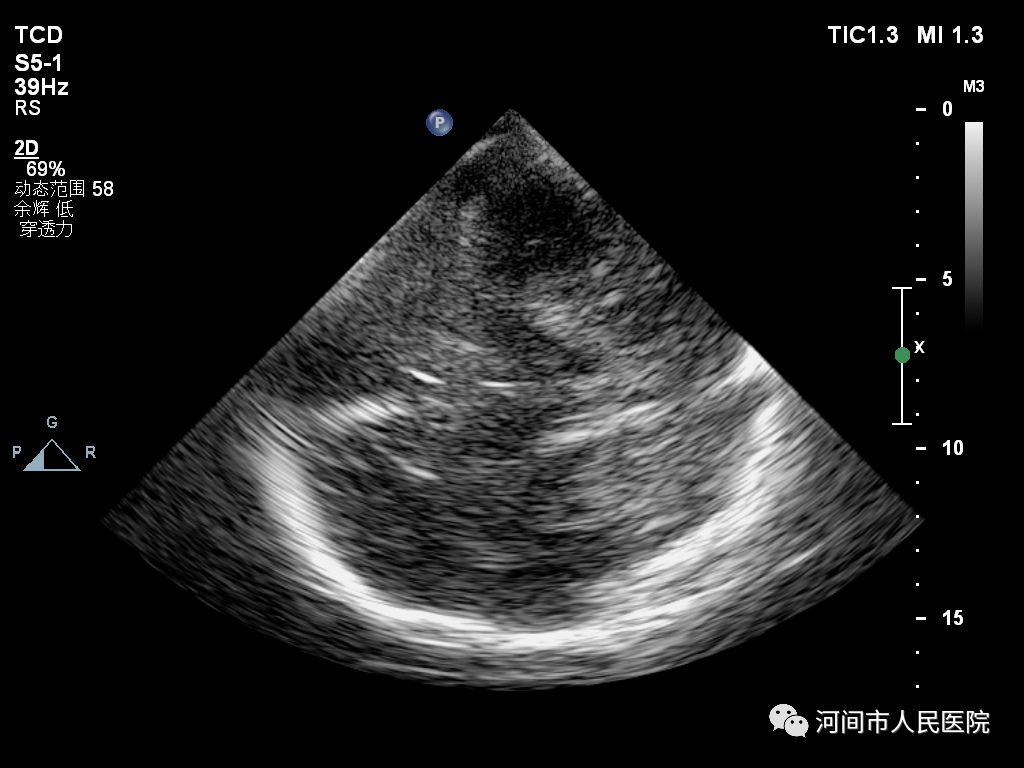

患者取仰卧位,检查者将探头紧贴于患者颅骨两侧颞窗进行检查。

正常的中脑黑质类似一只黑色的蝴蝶,其内部回声呈均质的低回声。

I级:呈均匀分布的低回声;Ⅱ级:见散在点状、细线状稍强回声;Ⅲ级:回声呈斑片状增强,低于脚间池回声;Ⅳ级:回声呈斑片状增强,等于脚间池回声;V级:回声呈斑片状增强,高于脚间池回声。